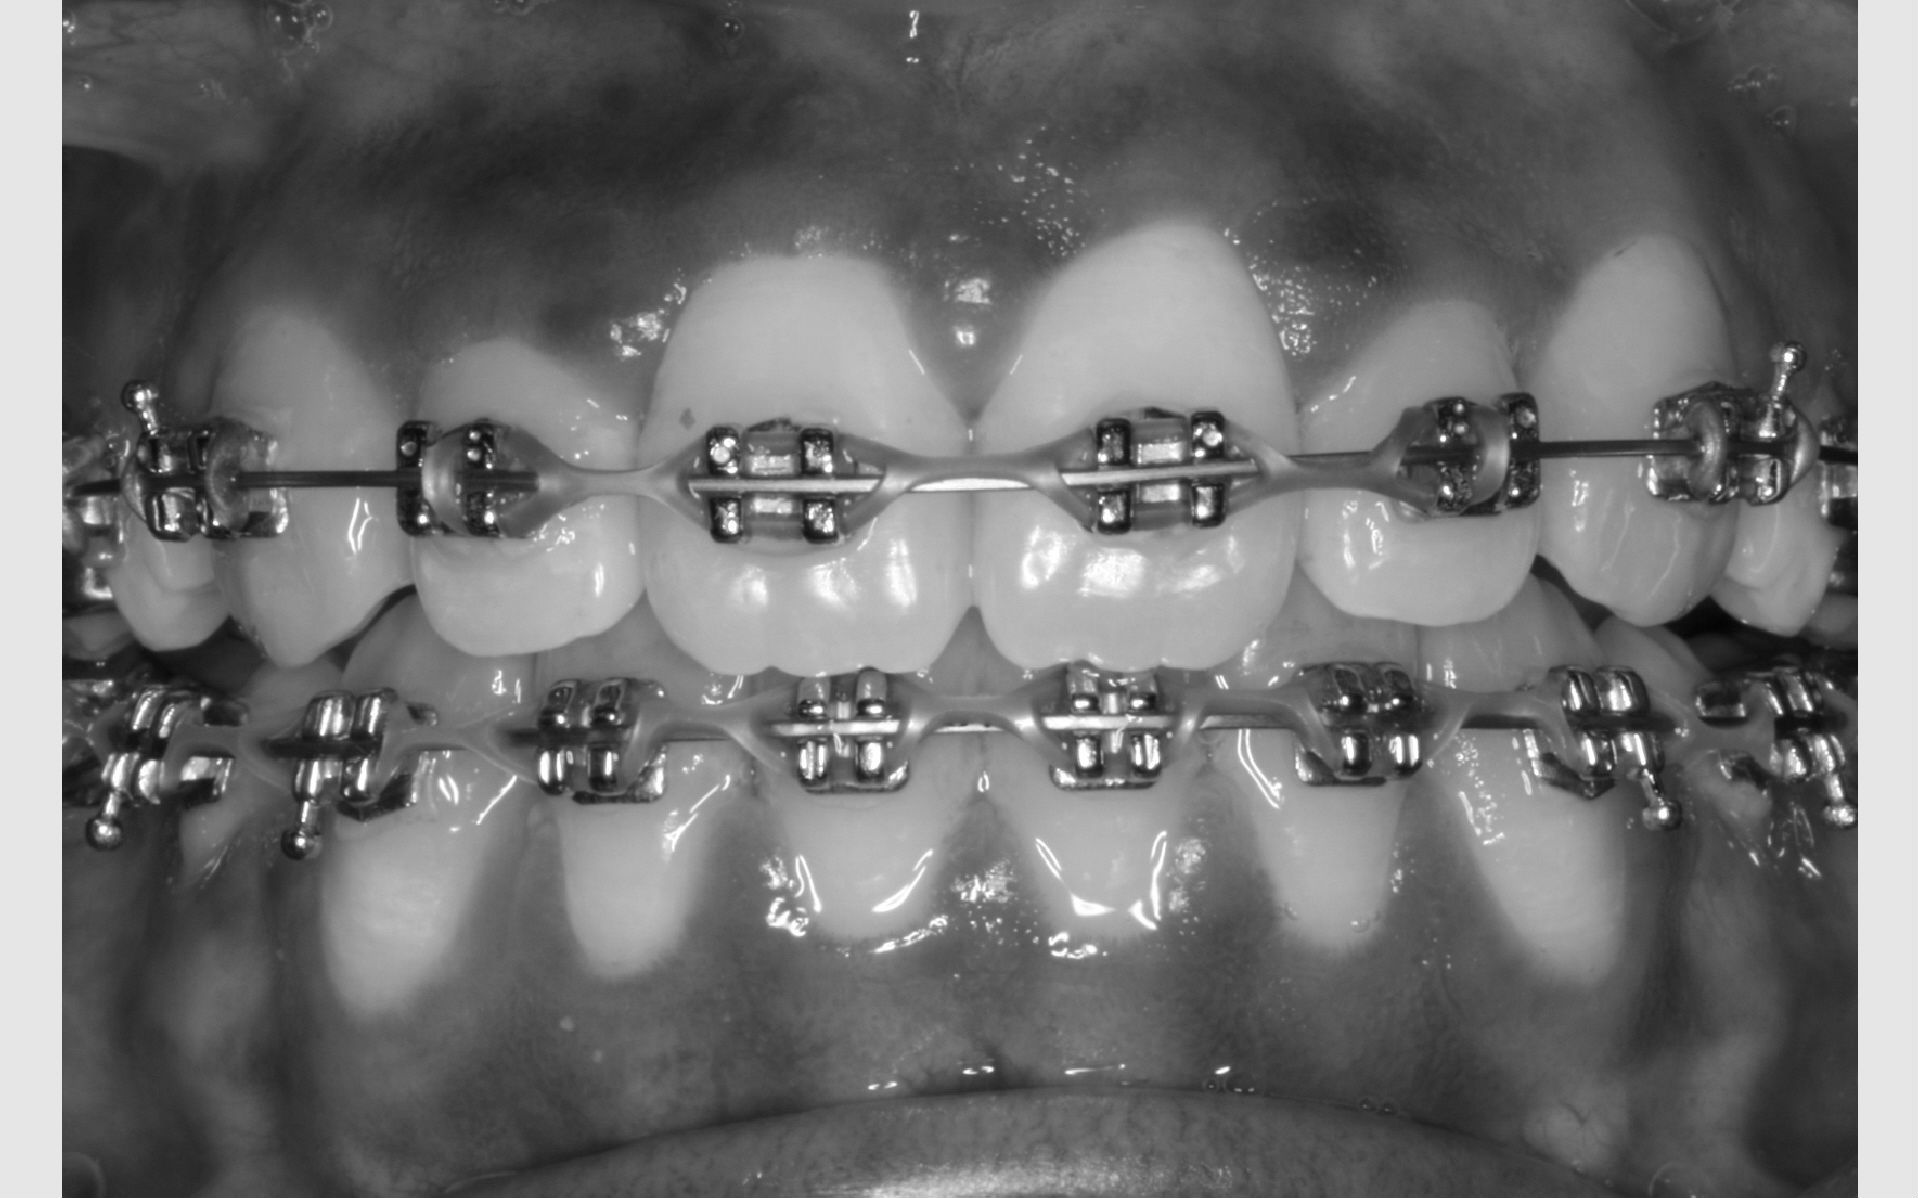

Faste bøjler - "togskinner"

Ofte er der brug for fastsiddende bøjler på tænderne. Mange kalder dem "togskinner", hvilket er et passende navn, da tænderne nærmest bliver flyttet i et spor på den lås, der limes på tanden.

Sådan bliver bøjlen sat på

Før låsene limes på, bliver tænderne pudset helt glatte. Herefter bliver overfladen gjort klar til limen med en blå gele, der skal ligge på tænderne i 30 sekunder. Der skylles med vand og blæses helt tørt, hvorefter låsene kan limes fat på tænderne. Limen er en form for plast, der svarer nogenlunde til den plast, man bruger til tandfyldninger.

For at plasten kan hærde, lyses der på tanden med ultraviolet lys i 20 sekunder. For at beskytte vores øjne mod det ultraviolette lys, bliver der holdt en orange skærm for øjnene. Når alle låse er limet på, forbindes de med en bue af metal. Det er den, der flytter på tænderne.